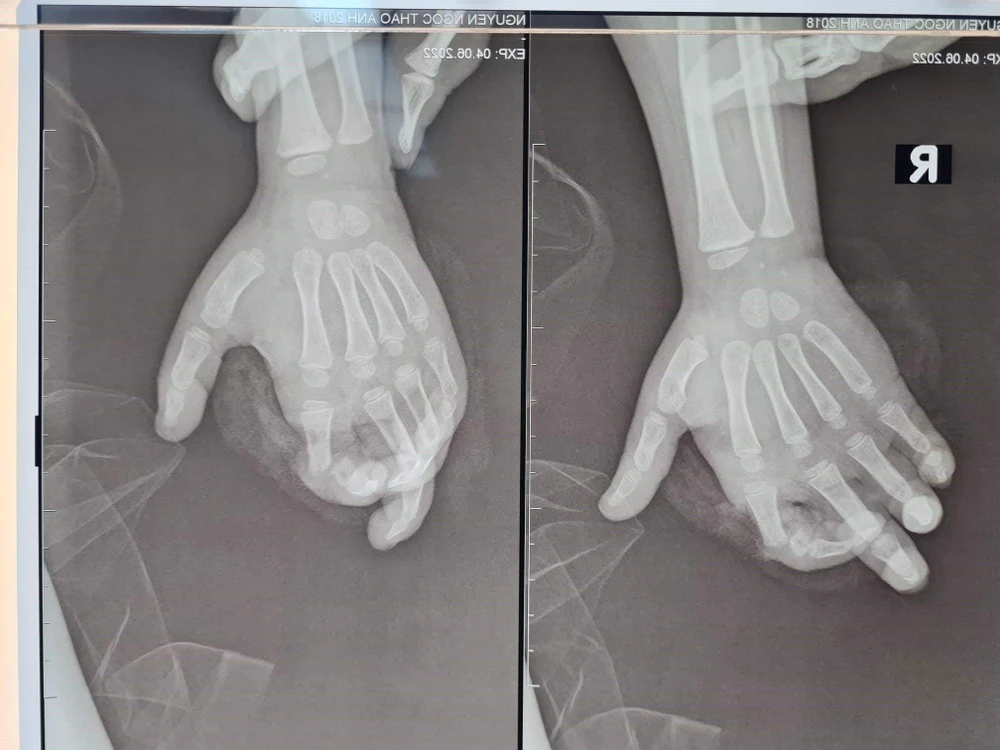

Sau tai nạn, bệnh nhi bị đứt gần rời ngón 2 tay phải (ngón 2 tay phải chỉ còn dính lại gân gấp), phần ngón đứt gần rời lủng lẳng, trắng bệch do không được cấp máu.

Hình ảnh ngón tay gặp tai nạn được chụp từ Xquang. Ảnh: BV |